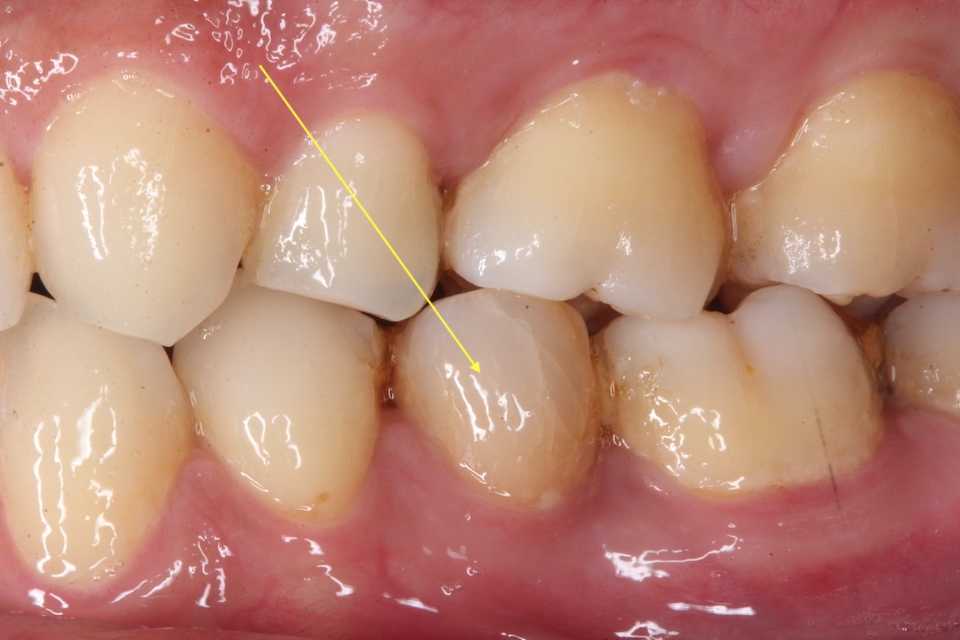

16歳女子、下顎後退位、両側性顎関節症で口が開かなくなって、近所の歯医者をハシゴしたが治らずうちに来た。ディープバイトというのは時折見かけるが、下顎が後方に変移していて、顎関節に負担がかかりやすい噛み合わせだ。少し前の方で噛める噛み合わせにしてあげると治る。見かけも同時に治る。では時系列でどうぞディープバイトは下の前歯が上の歯に隠れて見えない程に噛み合わせが深いということだ。下顎が後方に行き過ぎていることがほとんどなので、ちょっと前で噛めるようにしてあげると改善する。その噛み合わせの位置だと臼歯部に隙間ができるので、それを埋めるような歯列矯正をすれば良い。下顎の3、4間に上下的な段差があるので、ワイヤーが一直線に並べば良い。一直線に並ぶどころか、臼歯部をさらに揚げている。1年1ヶ月後治ったのでブラケットを外した。新しい噛み合わせに慣れたことを確認する。デュアルバイト(元の位置でも噛める)にならないように注意する。1年5ヶ月後3年後、まあまあ安定している。